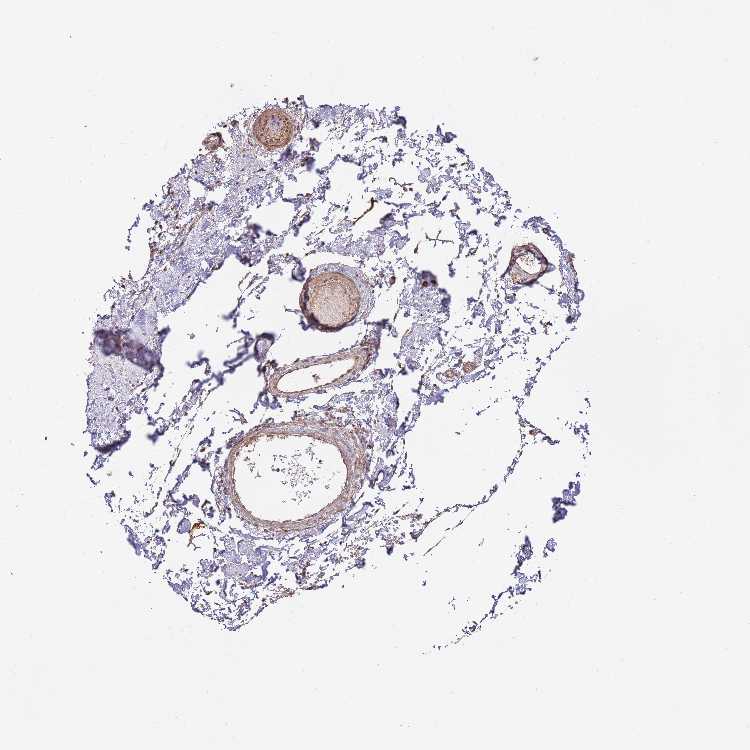

SOFT TISSUE 1 - Antibody stainingi

Antibody staining in the annotated cell types in the current human tissue is reported as not detected, low, medium, or high, based on conventional immunohistochemistry profiling in selected tissues. This score is based on the combination of the staining intensity and fraction of stained cells.

Each image is clickable and will lead to virtual microscopy that enables deeper exploration of all samples and also displays staining intensity scores, fraction scores and subcellular localization as well as patient and tissue information for each sample.

Antibody HPA042733Antibody CAB037186

Chondrocytes MediumMedium

Fibroblasts MediumNot detected

Peripheral nerve Not detectedNot detected